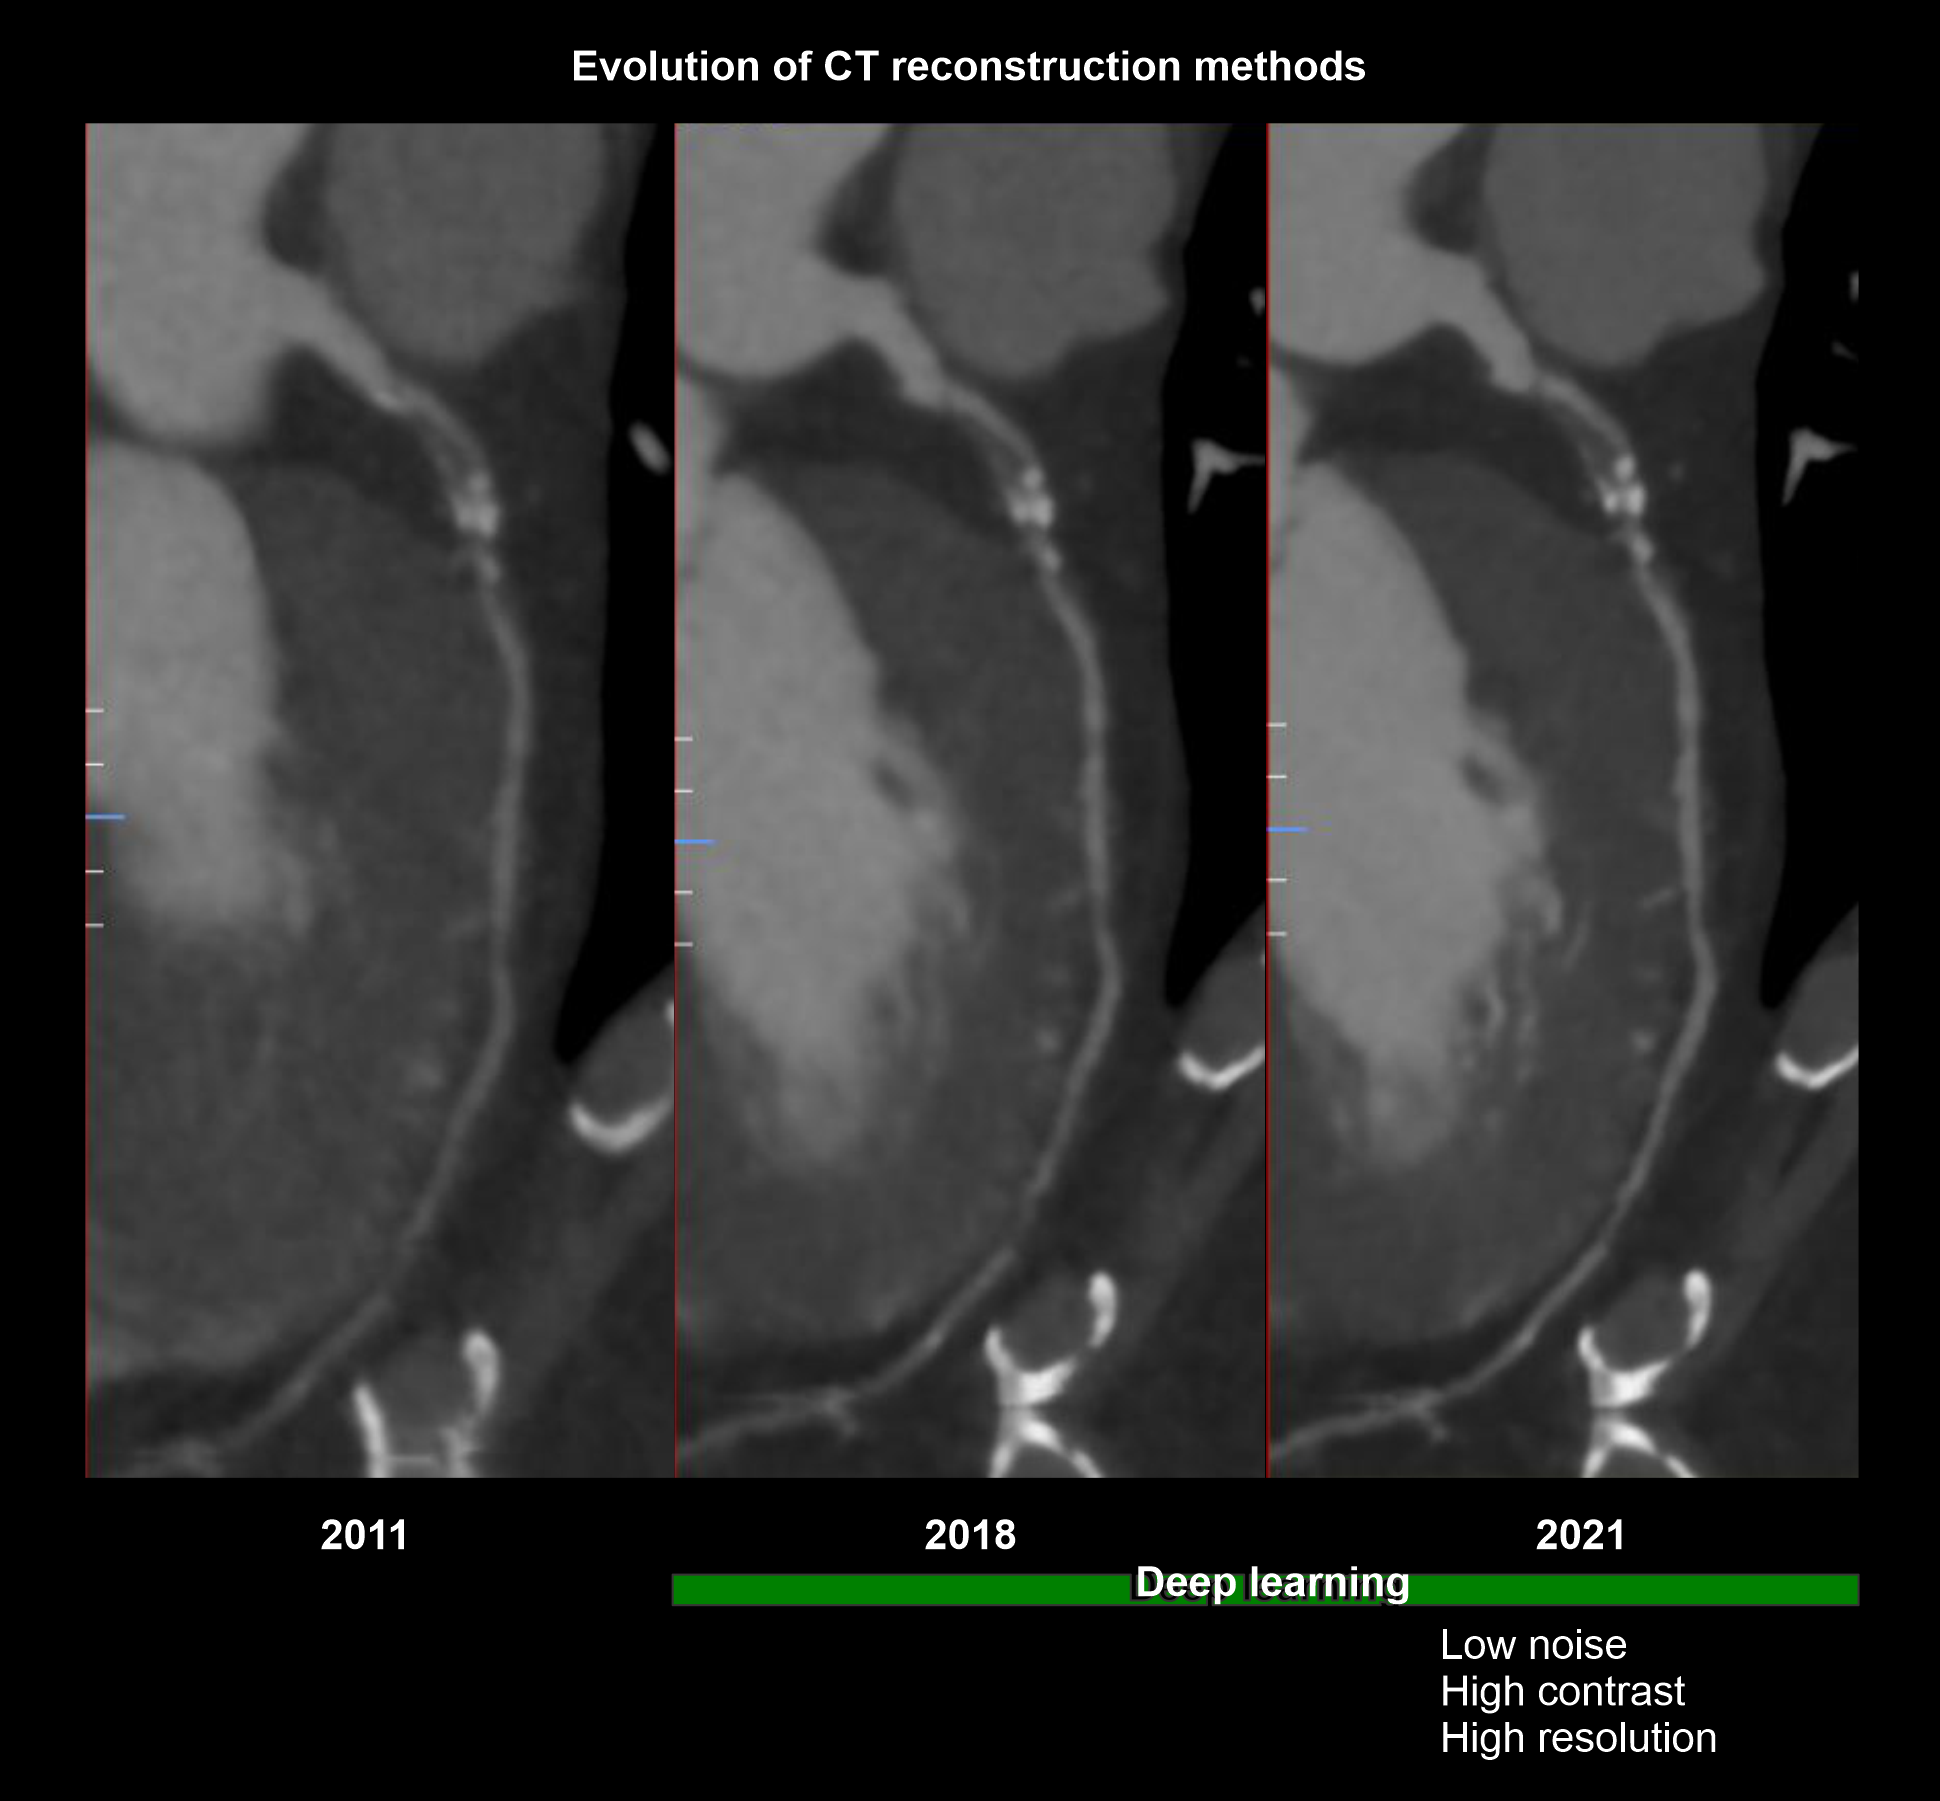

Explanation: when you plan for contrast injections, volume (mL) under flow rate (mL/s) should be nearly equal to 14 seconds or contrast volume must be injected to the patient within 14 seconds because prolonged injection may pool contrast in the right ventricle unnecessarily. Current high-tech scanners, with reconstruction methods powered by artificial intelligence (AI), has the ability to create vivid images utilizing lower contrast flow rate (4.5ml/s) and volume (65ml).